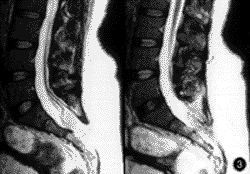

脂肪栓塞綜合徵細胞顱腦創傷:有頭部外傷史,可以表現為典型的昏迷——清醒——再昏迷病象,第二次昏迷往往逐漸發生,而且有顱腦高壓的表現;常有血壓增高,心率緩慢,呼吸減慢,臨終期才出現去大腦強直,腰椎穿刺、MRI、CT’等檢查有陽性表現。昏迷期可檢查出局部神經體徵。

2 大腦表現

發生率約86%。起始症狀包括譫妄不安、嗜睡和意識模糊,繼續發展可致昏迷。如治療及時,大部分病人可以完全恢復,但因大腦皮質的高敏感性可能留下不同程度的後遺症,輕者如個性變化、創傷後緊張綜合徵等,重者如四肢癱、癲等嚴重神經病理學障礙。合併頭部外傷的複雜骨折病人,其神經病理學表現的原因常難以確定,而受傷後至出現初期神經症狀的間隔時間有助於診斷。

(1)腦缺氧的預防:為保護腦功能,保證減少腦組織和全身耗氧量,降低顱內壓,防止高溫反應等作用,應給予頭部降溫或進行冬眠療法。更重要的是糾正低氧血症。